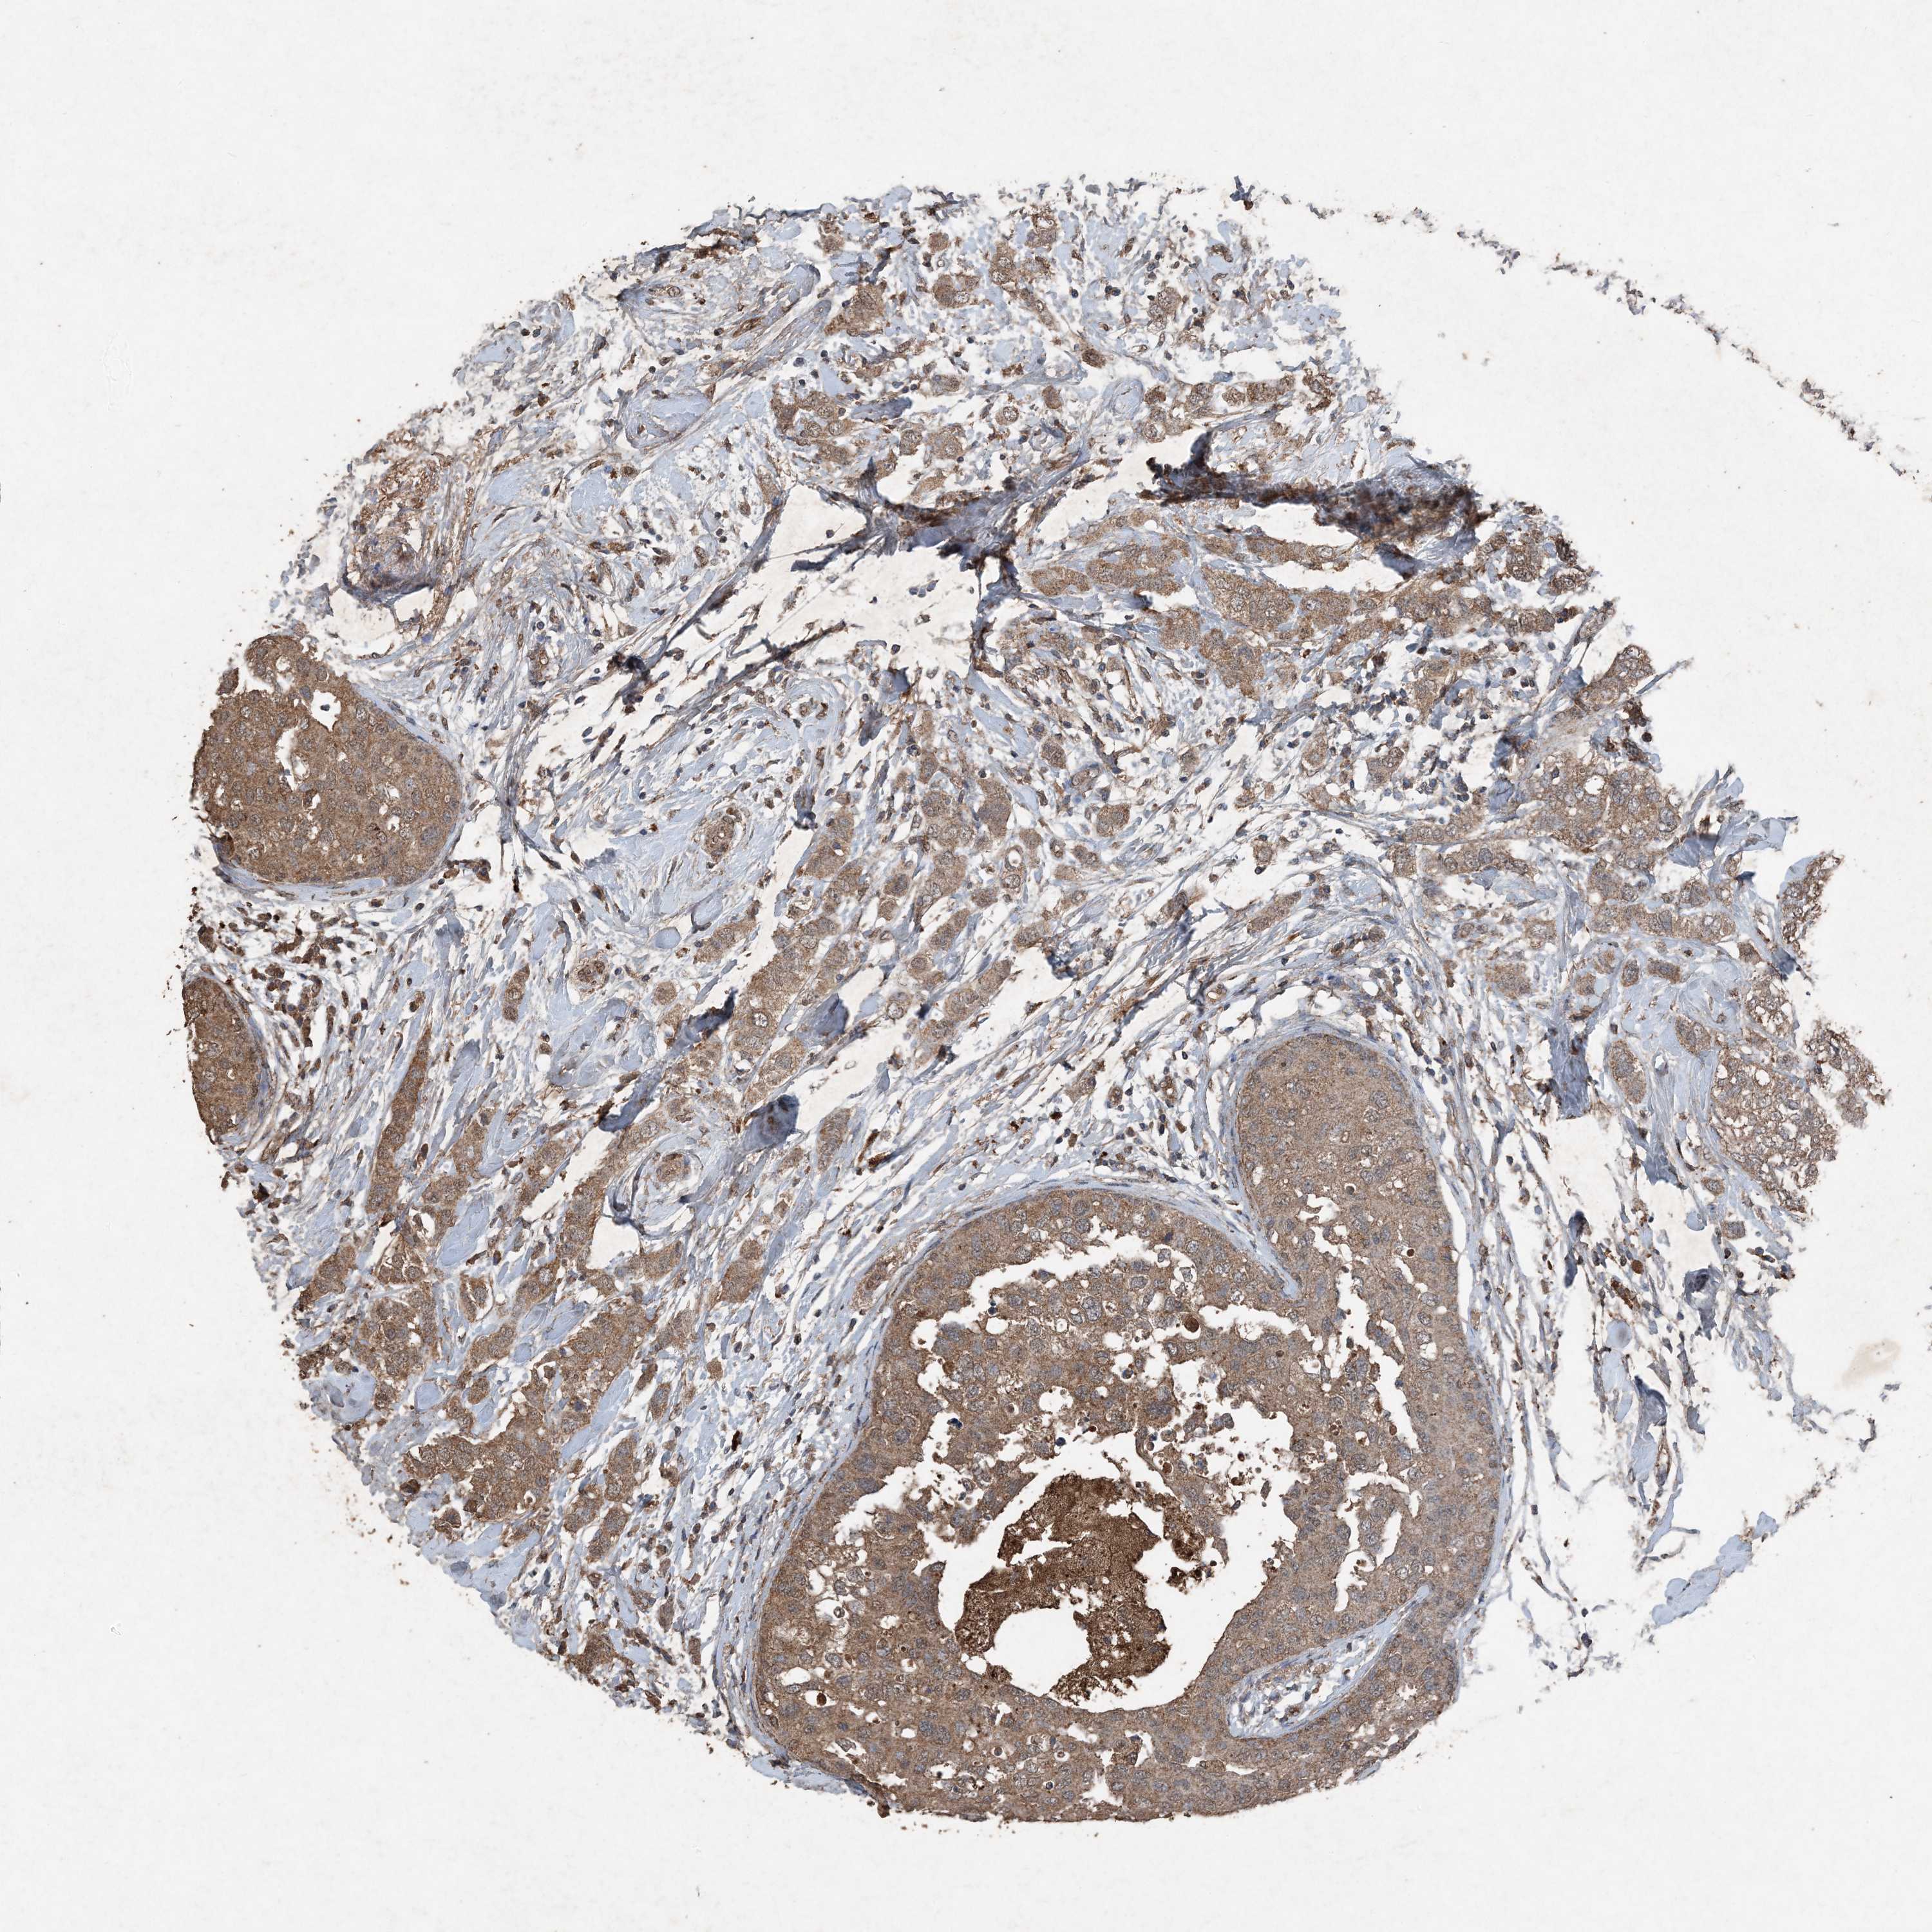

CANCER BREAST CANCER Show tissue menu

BRCA TCGA BRCA VALIDATION PROTEIN EXPRESSION